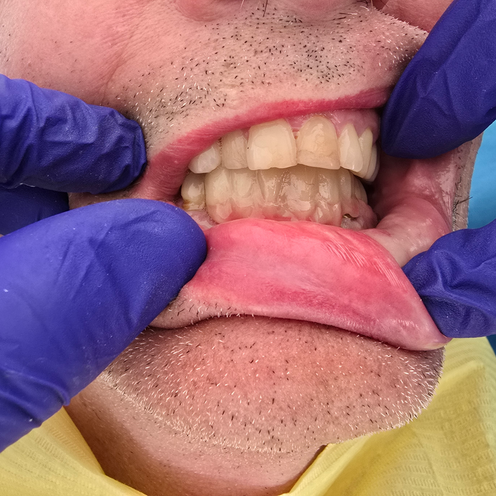

"De la frustration à la liberté : Comment le Dr. Iordan a transformé le sourire d’un patient avec un bridge en zircone sur 5 implants parfaitement placés !"

Imaginez un patient épuisé par la lutte quotidienne avec un dentier mobile inconfortable — un appareil qui glisse, irrite et transforme même les actions les plus simples, comme manger ou rire, en un véritable défi. Ça vous parle ? Eh bien, c’était le passé. Aujourd’hui, ce même patient est ravi, confiant et sans douleur, grâce à un bridge innovant en zircone, soutenu par cinq implants placés avec une précision millimétrique — une solution révolutionnaire signée par le Dr. Iordan, le spécialiste de confiance pour des solutions dentaires personnalisées et de classe mondiale, ici même, dans notre région.

Pourquoi ce bridge en zircone est-il le choix ultime ? Voici l’histoire : Quand un dentier mobile devient insupportable, la stabilité et le confort deviennent des priorités. Ce bridge en zircone, ancré sur cinq implants positionnés de manière stratégique, offre une fondation solide et équilibrée. Plus de glissements, plus d’irritations — juste une confiance totale pour manger, parler ou sourire.